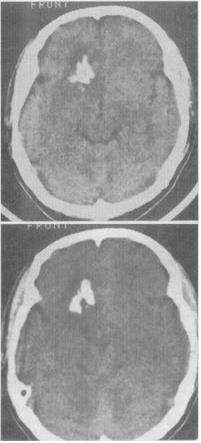

- 单项选择题 男性,28岁。阵发性四肢抽搐伴意识不清4次,每次持续数分钟,自行缓解。CT诊断(见图)最大可能是()。

A、脑囊虫并钙化

B、AVF

C、少枝胶质细胞瘤

D、室管膜瘤

E、脑实质内脑膜瘤

- C